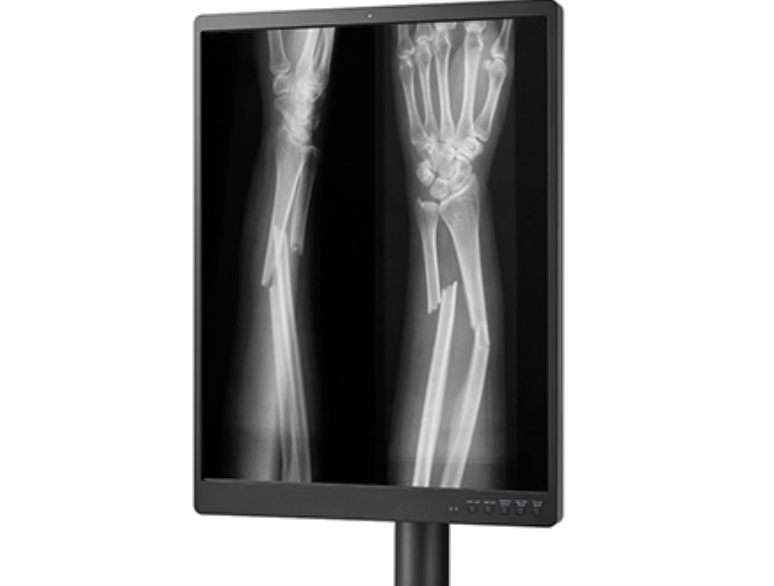

X-ray 사진은 기본 원리를 알면 꽤 흥미로워요. 뼈처럼 단단한 조직은 방사선을 거의 통과하지 않아 흰색으로 보이고, 근육이나 지방 같은 조직은 회색, 공기처럼 비어 있는 공간은 검정색으로 나옵니다. 그래서 폐는 검게, 갈비뼈는 하얗게 보이는 거죠. 물론 정밀한 판독은 전문가에게 맡겨야 하지만, 기본적인 구조만 알아도 진료를 이해하는 데 큰 도움이 돼요.

X-ray는 뼈를 보는 데는 아주 좋아요. 그래서 골절이나 관절염 같은 문제는 X-ray만으로도 충분히 확인할 수 있어요. 하지만 연골, 인대, 근육 같은 연부조직은 잘 안 보이죠. 이런 부분은 MRI가 훨씬 정밀하게 보여줘요. 예를 들어 허리디스크나 반월상연골파열 같은 문제는 MRI로만 확실히 확인이 가능해요. 저도 허리통증 있을 때 X-ray는 괜찮다고 했는데, MRI 찍고 나서야 디스크가 튀어나온 걸 확인했어요.

무릎 통증이 있을 땐 어떤 검사를 해야 할지 헷갈리죠. 넘어져서 아픈 경우라면 X-ray로 뼈에 이상이 있는지 확인하면 되고, 인대나 연골 같은 구조적인 문제가 의심되면 MRI가 필요해요. CT는 뼈의 미세한 손상을 자세히 볼 수 있어 골절 정밀 진단에 사용돼요. 무릎 연골이 찢어진 친구는 처음엔 X-ray로는 아무 이상 없었지만, MRI에서 연골파열이 발견됐어요.